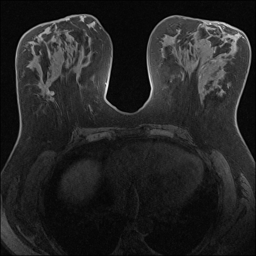

MRI images. The data used in this study are from the DUKE Breast Cancer Dataset [23], a comprehensive single-institutional retrospective collection of 3D MRI scans from over 900 patients with biopsy-confirmed invasive breast cancer at a university hospital. Each study includes a 3D MRI acquired using 1.5T or 3T scanners, from patients in the prone position. On average, each 3D scan consist of 250 2D slices (see Figure 1). For the predictive tasks, the slices are categorized into two groups: those containing breast tumors and those without. Following the approach of [15, 12], we establish a buffer zone between slices containing tumors and those that do not (highlighted in yellow in Figure 1(a)). Images within this buffer zone are excluded from analysis, and the remaining slices are labeled and used for the predictive task.

Magnetic field strength. 3T scanners offer higher magnetic field strength, improving signal-to-noise ratio (SNR) and image resolution for sharper, more detailed images [24]. However, they are more prone to artifacts, heating effects, and signal loss, especially around metal implants [5]. As such, our proposed dataset involving this spurious signal features a non-local spurious signal that influences the entire image rather than a localized region. An example set of images obtained from 1.5T and 3T devices are provided in Figure 3, showing that it is visually not possible to distinguish 1.5T MRIs from the 3T ones.